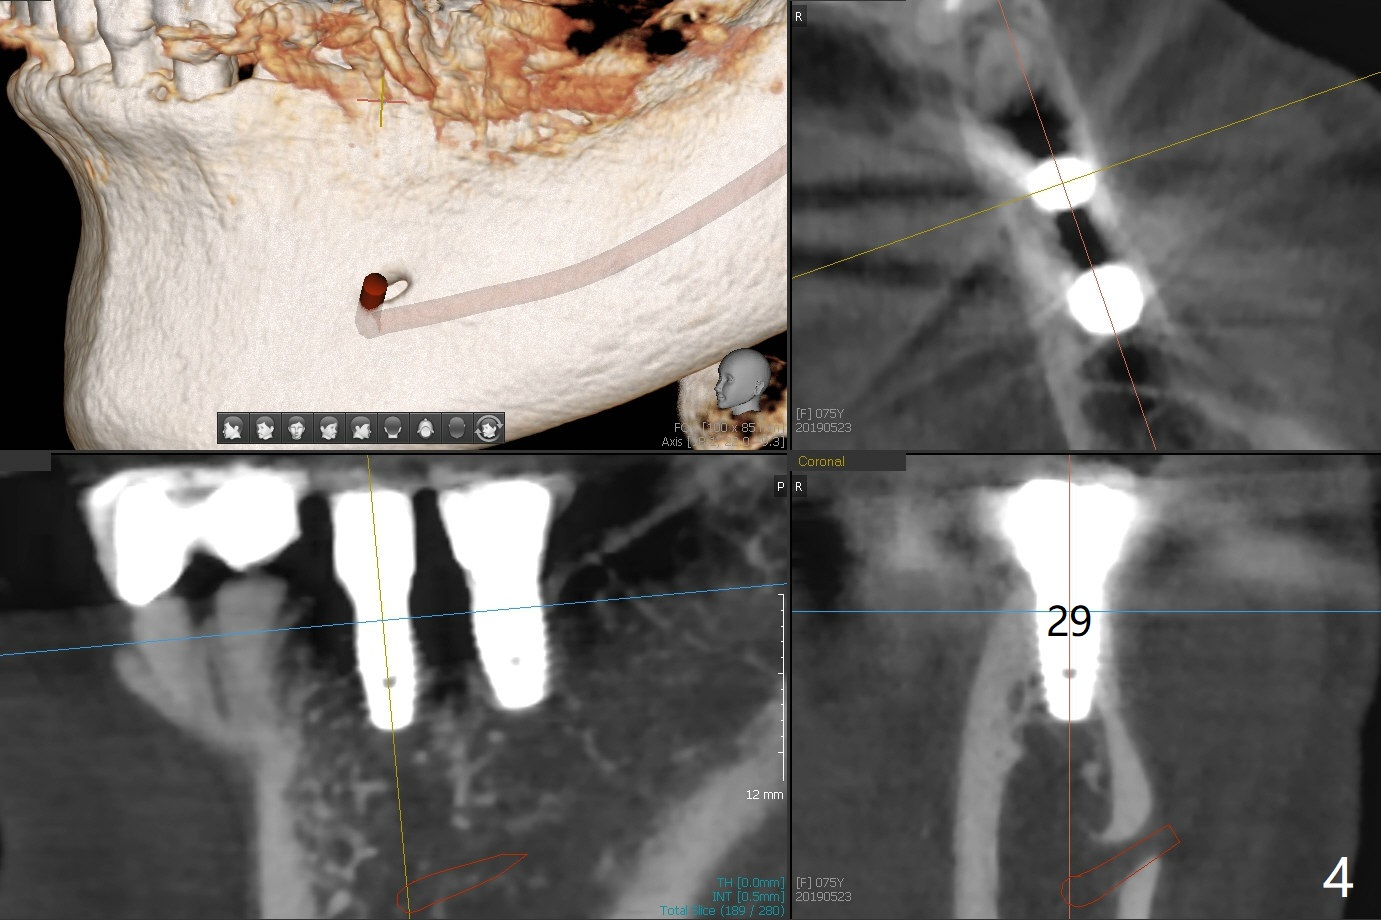

When the 75-year-old woman presents to clinic with #25 mobility, she is also concerned about gingival hemorrhage. It appears that the buccal plate is lost at #10 and 30 (Fig.2,3), as compared to #7, 19, 20 (Fig.1,4,5). Block graft may be required (Fig.6,7 for #10 for example). In fact there is tenderness buccal to the implant at #30. The patient has been using water pik and will carry it while traveling.